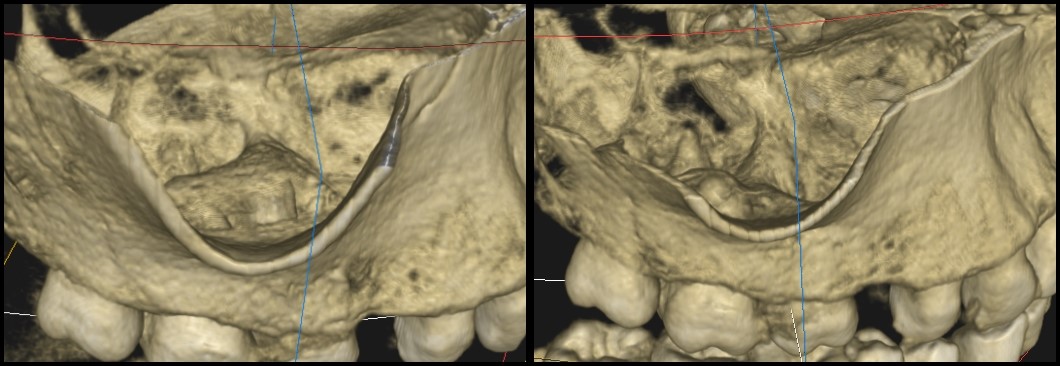

Ryc. 5. Rekonstrukcja 3D – obraz zmiany z boku.

Ryc. 6. Rekonstrukcja 3D – obraz zmiany z góry.

Kanały policzkowe udało się opracować i wypełnić do 1/3 wierzchołkowej, dalsze części kanałów były całkowicie zobliterowane. W trakcie opracowywania kanału podniebiennego zauważono wyciek żółtego opalizującego płynu spoza wierzchołka korzenia zęba, który po kilku minutach samoistnie ustał. Zasugerowało to obecność torbieli korzeniowej. Po zakończeniu leczenia endodontycznego wykonano zdjęcie punktowe kontrole (ryc. 2) oraz tomografię komputerową wiązki stożkowej (cone beam computed tomography – CBCT) opisywanego zęba. Jej rezultat przedstawiają ryciny 3‑6. Widzimy na nich znacznych rozmiarów torbiel korzeniową, która w toku leczenia musi zostać usunięta. Ustalono rozpoznanie ostateczne – torbiel okołowierzchołkowa. Omówiono z pacjentem jego stan i zaproponowano dalsze leczenie, na które wyraził zgodę.